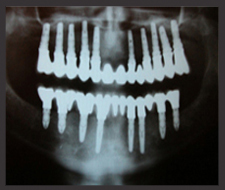

Dental implants are like artificial roots of theet which are placed into the jaw. Dental implants are giving the support for crowns, bridges and removable dentures. This is a wonderful solution, because we can implant the artificial root into the place of the lost tooth thus after healing it can take over the original function.

We need to see the patients and their x-rays before we can give a decent quotation.